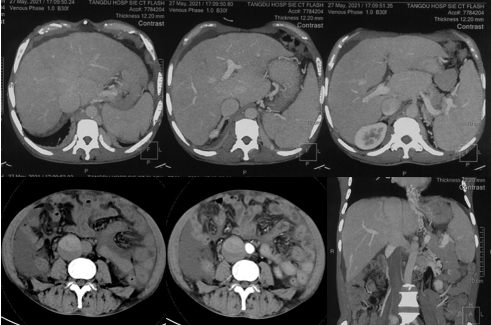

6月20日,患者及家屬懷揣著忐忑的心情來(lái)到西安國(guó)際醫(yī)學(xué)中心醫(yī)院找到韓國(guó)宏教授,韓教授詢問(wèn)病情后閱患者外院CT片,明確診斷布加綜合征,同時(shí)發(fā)現(xiàn)了一個(gè)新的問(wèn)題,在詢問(wèn)病史時(shí)了解到患者近一周雙下肢乏力伴腫脹明顯加重,遂立即安排了急診CT,證實(shí)下腔靜脈內(nèi)急性血栓形成!

6月22日,在韓國(guó)宏教授的帶領(lǐng)下,患者于消化介入診療中心行下腔靜脈開(kāi)通術(shù)。術(shù)中可見(jiàn):下腔靜脈全段擴(kuò)張,膜性閉塞,腎靜脈平面以下可見(jiàn)血栓形成并伴有粗大的側(cè)枝靜脈,遂對(duì)狹窄段球囊擴(kuò)張并植入支架,術(shù)后下腔靜脈血流通暢,側(cè)枝消失。術(shù)后第2天,患者腹壁靜脈曲張幾乎消失不見(jiàn),走路也輕快了許多。明明只是薄薄的一層膜,為什么開(kāi)通起來(lái)這么難?韓教授指出,盡管布加綜合征介入開(kāi)通技術(shù)已使創(chuàng)傷降到了最低,但受到患者個(gè)體差異及醫(yī)療水平參差不齊的限制,仍有可能出現(xiàn)嚴(yán)重的并發(fā)癥,主要包括:心包積血、縱隔血腫、心包填塞甚至下腔靜脈撕裂引起的大出血等。而其發(fā)生率與術(shù)者的操作熟練程度及經(jīng)驗(yàn)有很大的關(guān)系。